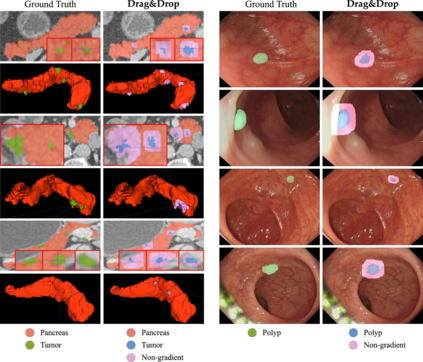

Creating large-scale and well-annotated datasets to train AI algorithms is crucial for automated tumor detection and localization. However, with limited resources, it is challenging to determine the best type of annotations when annotating massive amounts of unlabeled data. To address this issue, we focus on polyps in colonoscopy videos and pancreatic tumors in abdominal CT scans; both applications require significant effort and time for pixel-wise annotation due to the high dimensional nature of the data, involving either temporary or spatial dimensions. In this paper, we develop a new annotation strategy, termed Drag&Drop, which simplifies the annotation process to drag and drop. This annotation strategy is more efficient, particularly for temporal and volumetric imaging, than other types of weak annotations, such as per-pixel, bounding boxes, scribbles, ellipses, and points. Furthermore, to exploit our Drag&Drop annotations, we develop a novel weakly supervised learning method based on the watershed algorithm. Experimental results show that our method achieves better detection and localization performance than alternative weak annotations and, more importantly, achieves similar performance to that trained on detailed per-pixel annotations. Interestingly, we find that, with limited resources, allocating weak annotations from a diverse patient population can foster models more robust to unseen images than allocating per-pixel annotations for a small set of images. In summary, this research proposes an efficient annotation strategy for tumor detection and localization that is less accurate than per-pixel annotations but useful for creating large-scale datasets for screening tumors in various medical modalities.